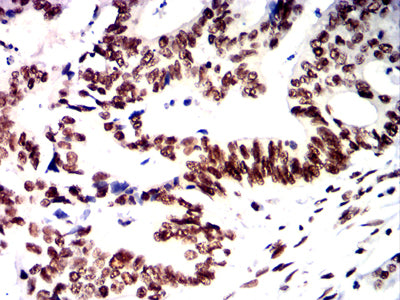

Immunohistochemical analysis of paraffin-embedded human rectal cancer tissues using PMS2 mouse mAb with DAB staining.